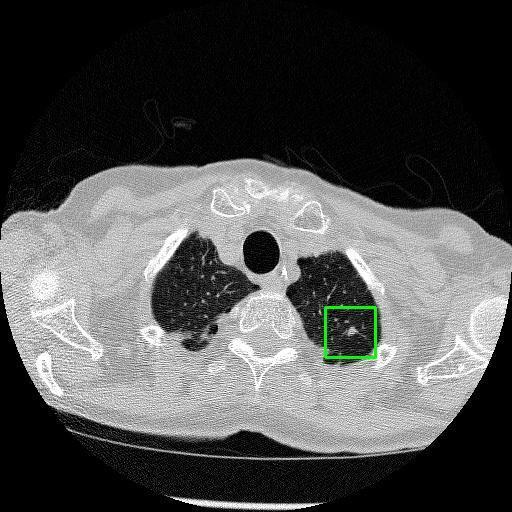

We developed an AI-based system using deep learning models for analyzing lung CT scans to detect and classify pulmonary nodules. We chose the YOLOv11 architecture for its enhanced object detection capability and adapted it specifically for medical imaging, incorporating pixel-level precision and severity classification.

Classification into three severity levels with colored bounding boxes.

Successfully built and deployed an AI model (YOLOv11) capable of detecting lung nodules in CT scans with high accuracy and real-time performance.

Designed a severity classification system that categorizes nodules into null, moderate, and severe using colored bounding boxes, assisting in rapid clinical decision-making.